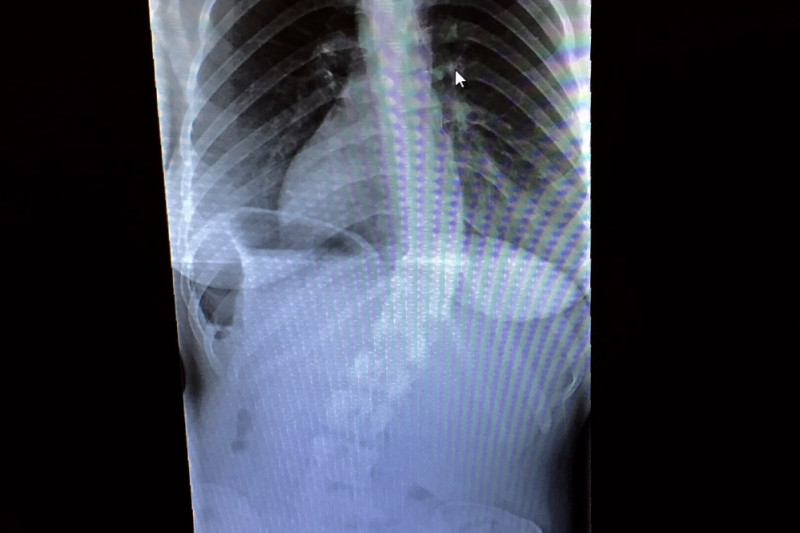

As some of you may know, Allyn has had severe scoliosis her entire life. Six years ago it was discovered that she had a 32 degree curve on her spine. Two months ago she had more x-rays taken along with MRIs that showed an increase in the curve to 47 degrees, making it a mandatory surgery. Though she may seem fine from her appearance, this degree of scoliosis is extremely painful which makes it difficult to go about her day to day activities.